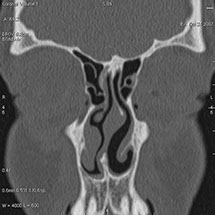

Cet appareil permet de faire des images en coupe du corps humain

et de les reconstruire dans différents plans pour mieux visualiser

et comprendre les pathologies. L’examen nécessite parfois une préparation

particulière et l’injection d’un produit de contraste pas voie

intra-veineuse.

Les renseignements apportés par cet examen sont très souvent

déterminants pour porter un diagnostic précis.

Le scanner comporte un lit d'examen, sur lequel le patient est allongé, qui va se déplacer lentement pendant l’examen et un anneau qui va tourner autour du patient en émettant des rayons X (il contient le tube à rayons X et les récepteurs). Les rayons X vont traverser la région à étudier et permettre d’obtenir des images en coupe de la zone à étudier. Des traitements de numérisation informatique permettront d'obtenir  des images 2D ou 3D dans différents plans et volumes.

Grâce aux scanners multidétecteurs (ou multi-barrettes) à acquisition spiralée, on obtient une exploration très précise d'un large volume du corps humain pour un temps d'acquisition de quelques dizaines de secondes.